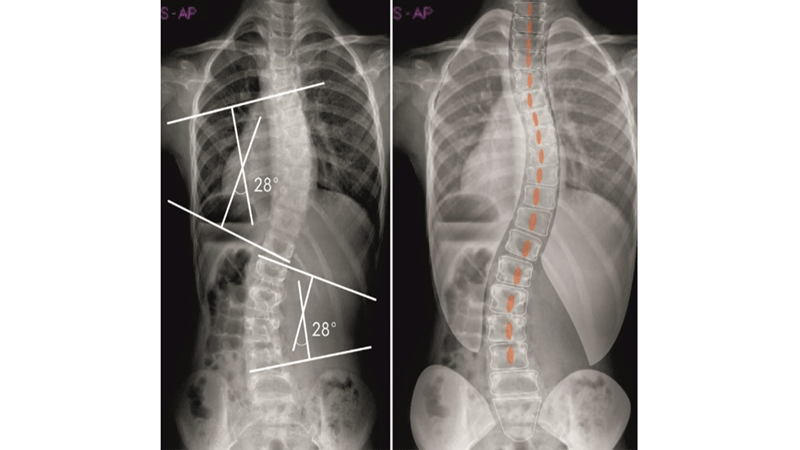

Fizyoterapist Adnan Nalbant: Skolyozun varlığının ortaya konması çeşitli radyolojik incelemeler vasıtası ile gerçekleştirilebilir. Çeşitli açılardan çekilenx-ray grafiler, ilk olarak başvurulan görüntüleme yöntemidir.

Görüntüleme yöntemleri ile omurganın eğriliğinin derecesi değerlendirilir. Kişide skolyoz varlığından bahsedilmesi için eğriliğin en az 10 derece tespit edilmesi gerekir.